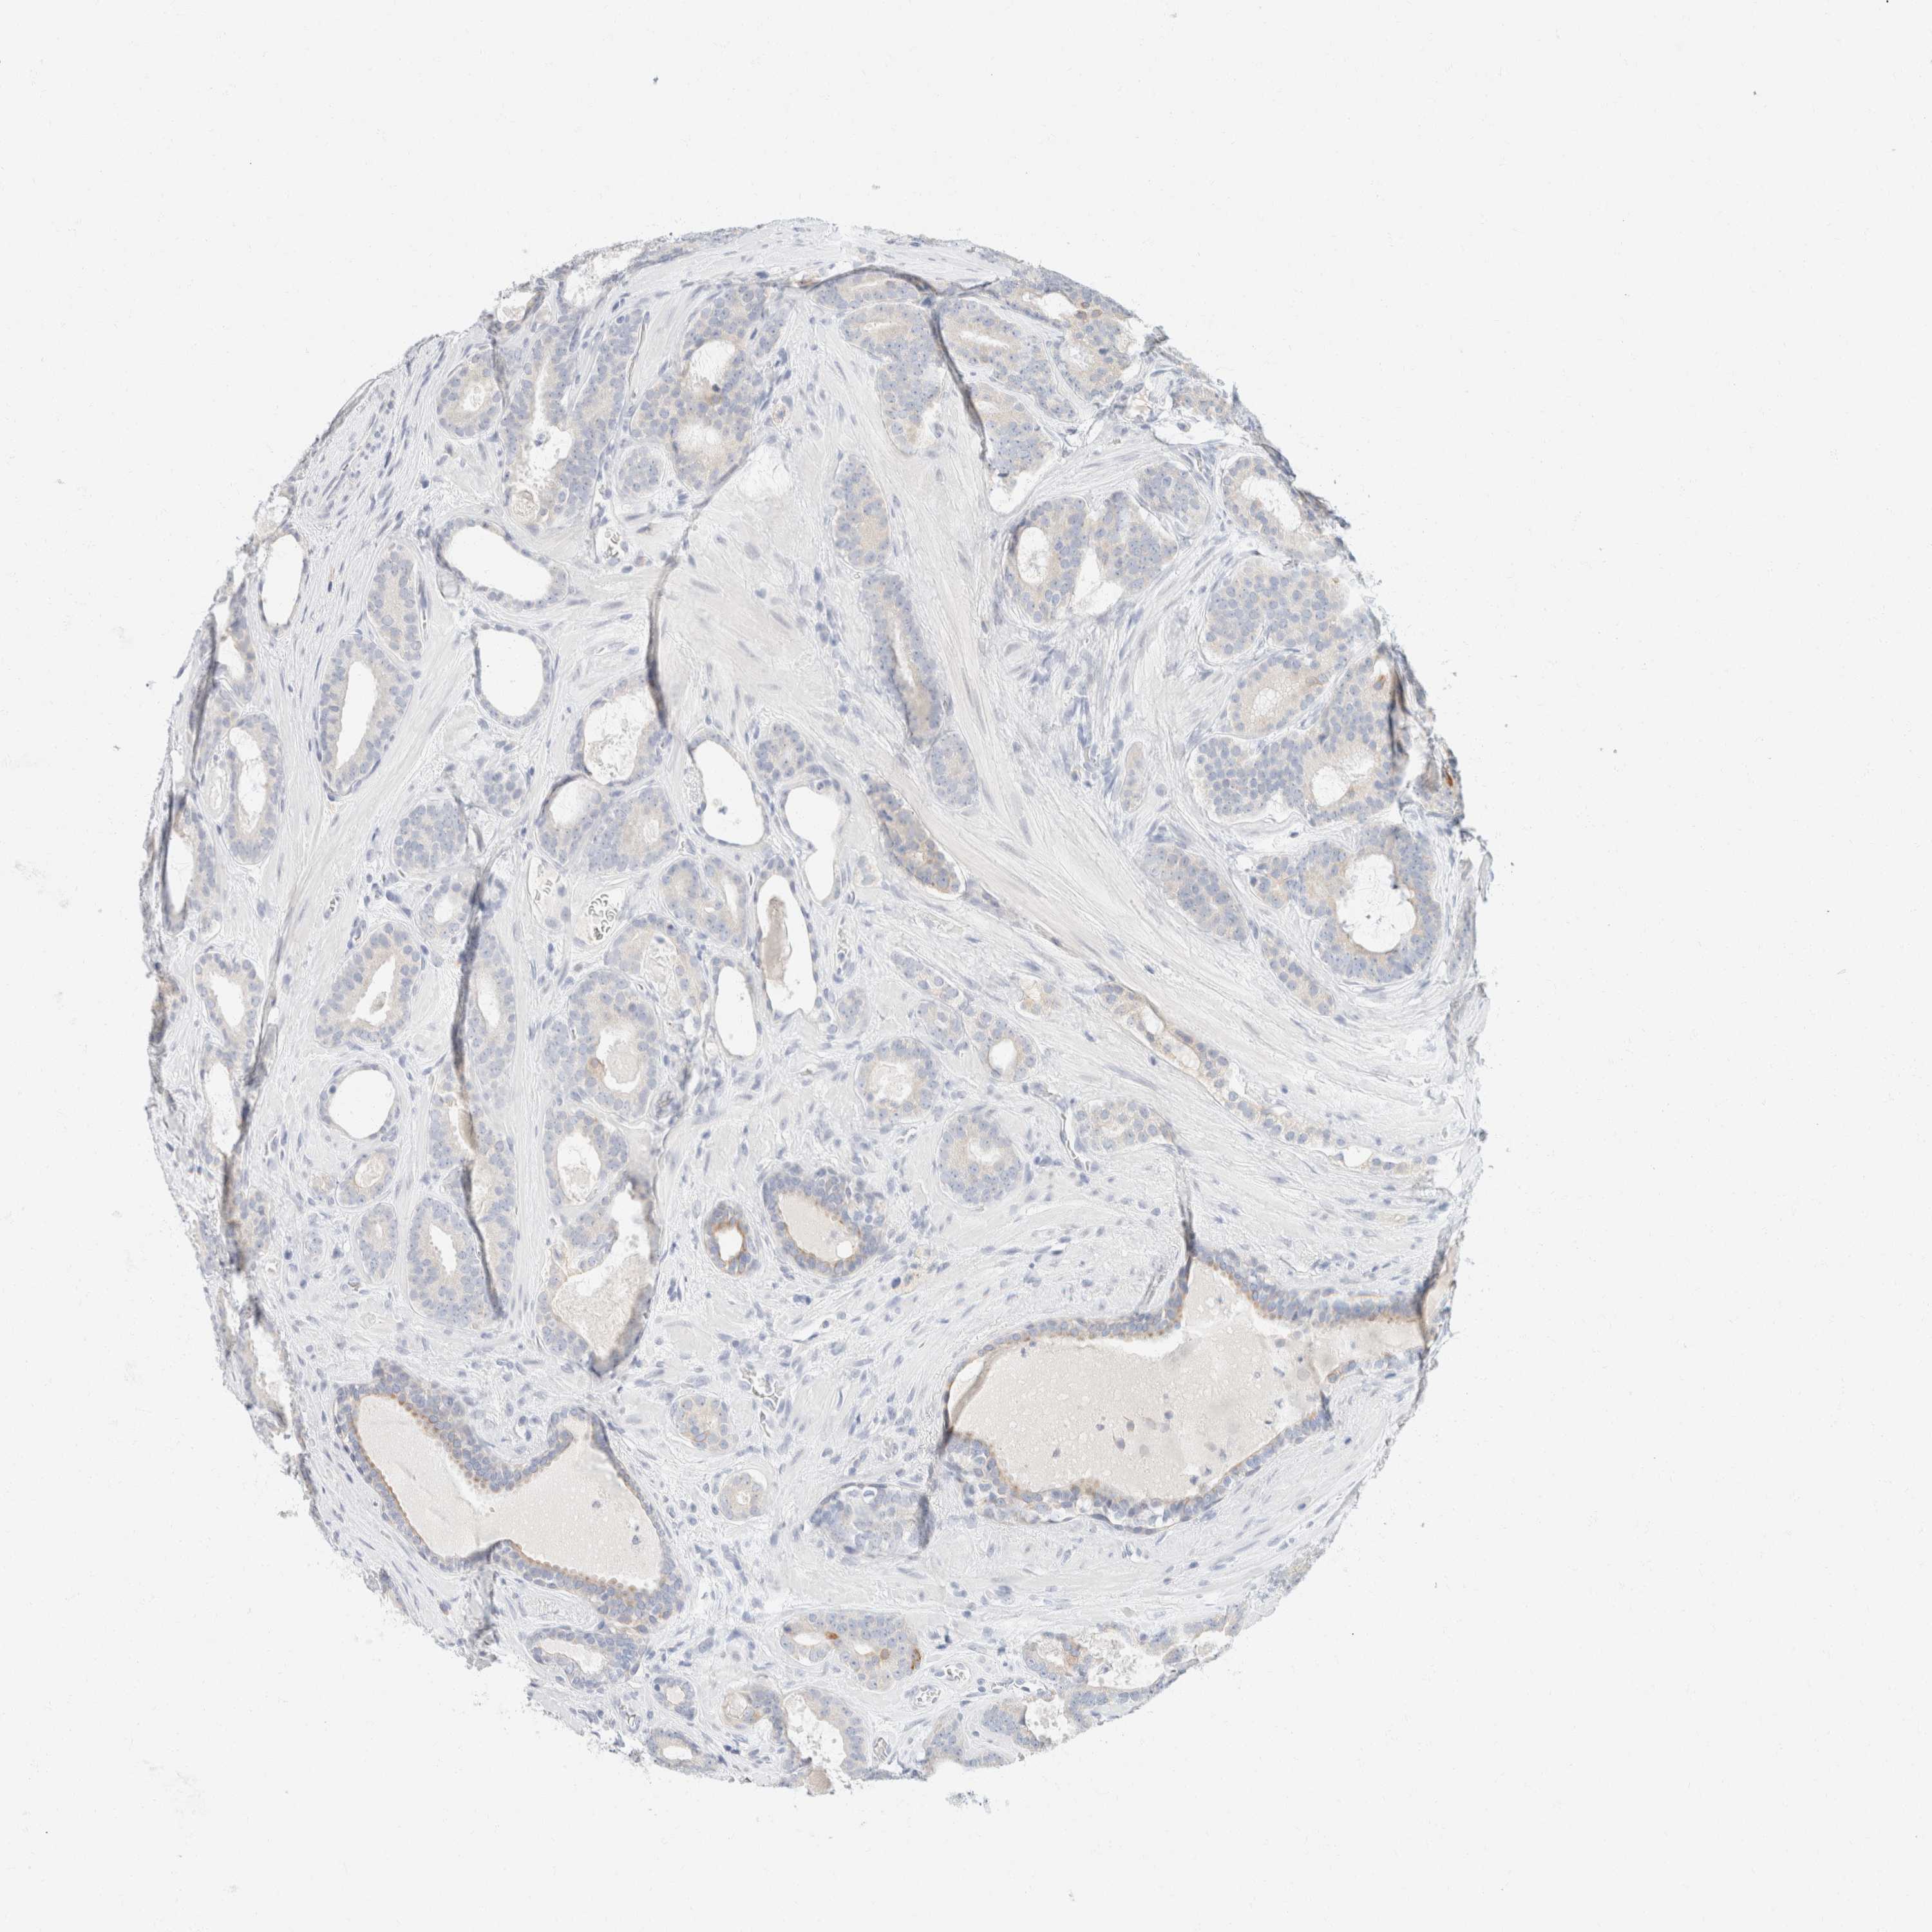

PROSTATE CANCER - Protein expressioni

A mouse-over function shows sample information and annotation data. Click on an image to view it in a full screen mode. Samples can be filtered based on level of antibody staining by selecting one or several of the following categories: high, medium, low and not detected. The assay and annotation is described here.

Note that samples used for immunohistochemistry by the Human Protein Atlas do not correspond to samples in the TCGA dataset.

Antibody stainingi

Antibody staining in the annotated cell types in the current human tissue is reported as not detected, low, medium, or high, based on conventional immunohistochemistry profiling in selected tissues. This score is based on the combination of the staining intensity and fraction of stained cells.

Each image is clickable and will lead to virtual microscopy that enables deeper exploration of all samples and also displays staining intensity scores, fraction scores and subcellular localization as well as patient and tissue information for each sample.

Antibody HPA024309

Antibody HPA024684

Antibody HPA027236

Antibody CAB000032

Staining

High

Medium

Low

Not detected

Intensity

Strong

Moderate

Weak

Negative

Quantity

>75%

75%-25%

<25%

None

Location

Nuclear

Cytoplasmic/membranous

Cytoplasmic/membranous,nuclear

Adenocarcinoma, High grade

Adenocarcinoma, Low grade

Adenocarcinoma, Medium grade